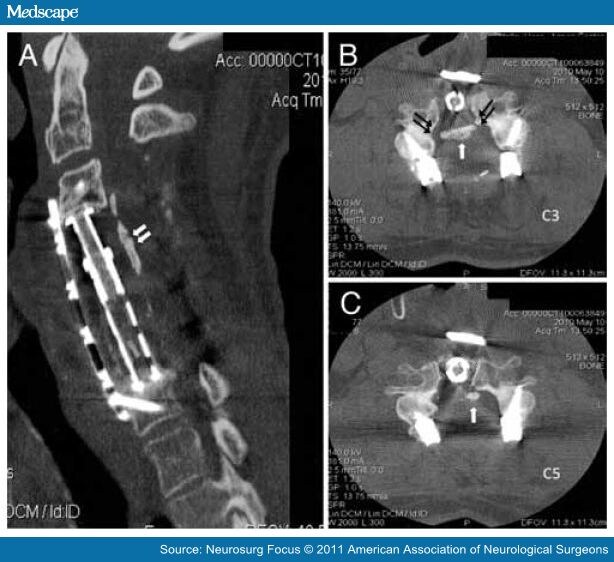

Figure 2 from Surgical Treatment for Ossification of the Posterior

From www.medscape.com